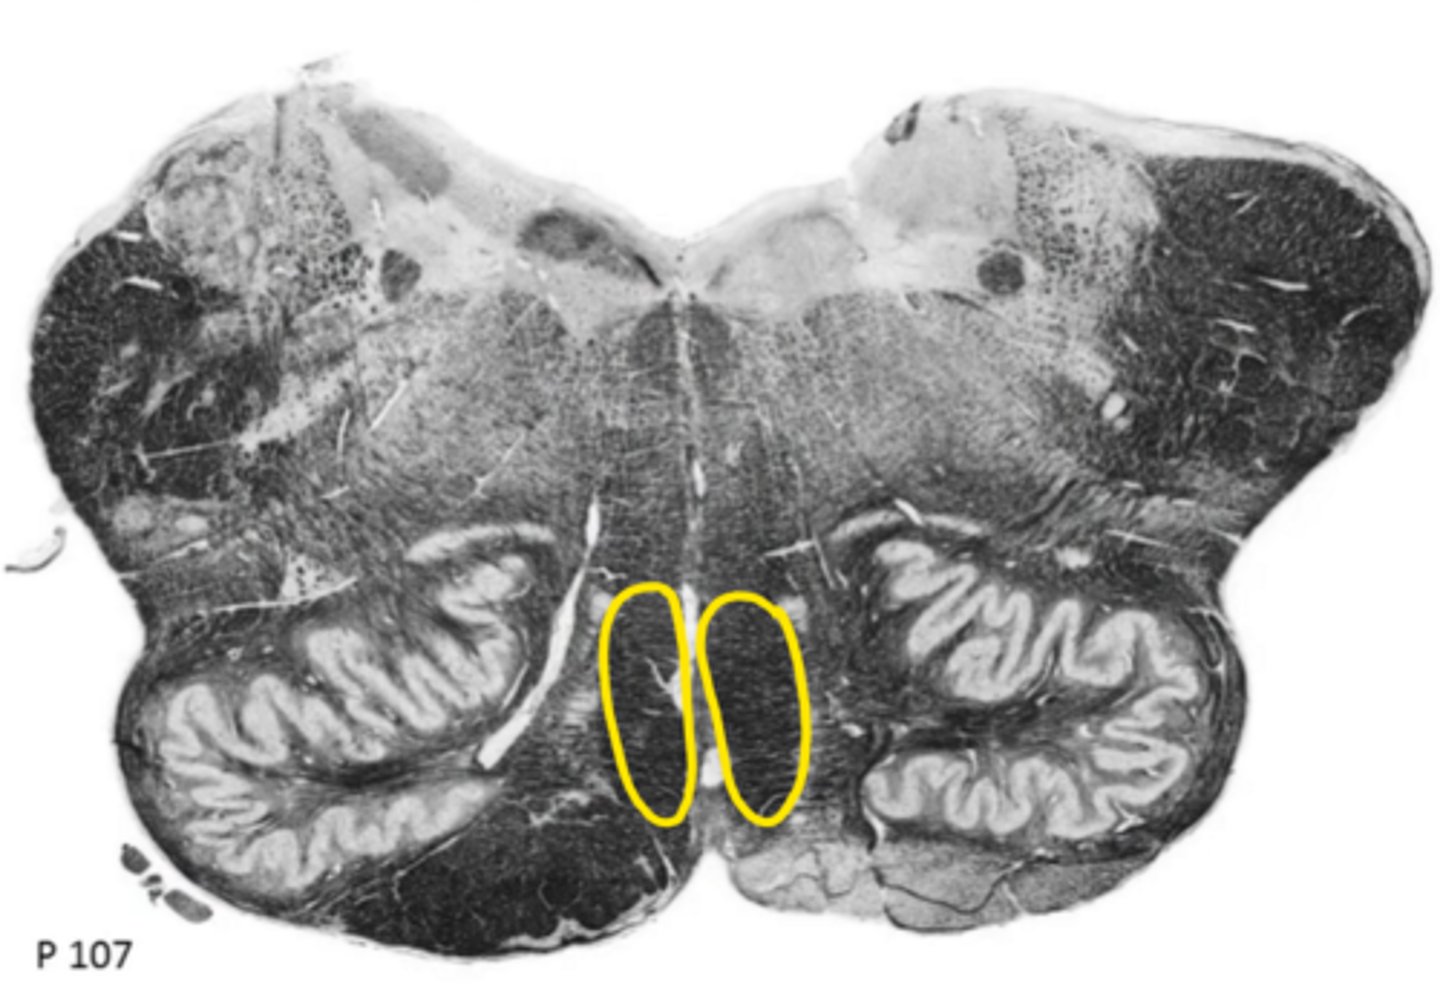

fourth ventricle

ID the space

hypoglossal nucleus

ID the nucleus

vestibular nucleus

inferior cerebellar peduncles

ID the structure

reticular formation

vagus nerve

ID the nerve

principle olivary nucleus

corticospinal fibers

hypoglossal nerve

medial lemniscus

anterior median sulcus